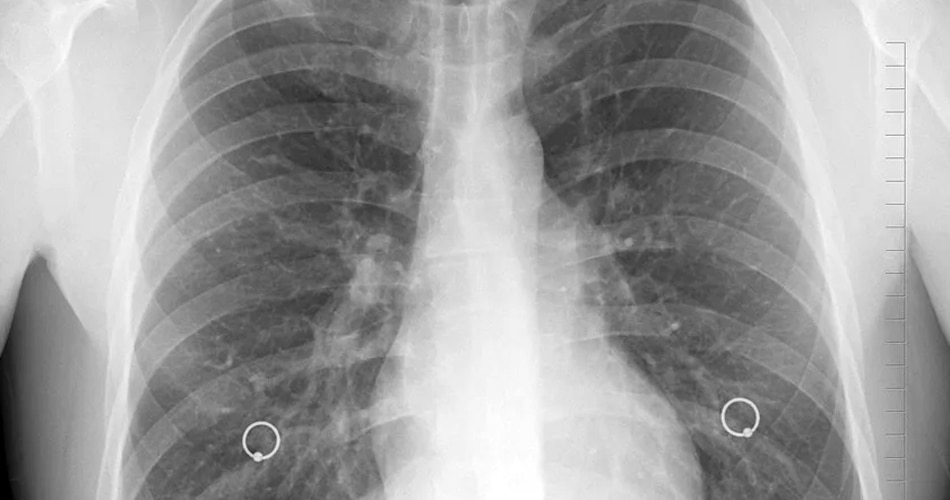

स्मोकिंग का शरीर पर बहुत बुरा असर पड़ता है. इससे शरीर में फेफड़ों का कैंसर, दिल की बीमारी, एम्फाइज़िमा या फिर अन्य तरह की दिक्कतें होने लगती हैं. औसतन स्मोकिंग ना करने वालों की तुलना में स्मोकिंग करने वालों की मौत भी जल्दी हो जाती है. कुछ लोग लाख कोशिशों के बाद भी स्मोकिंग करना नहीं छोड़ पाते हैं और इसके पीछे उनकी कुछ गलतफहमियां हैं. आइए जानते हैं इसके बारे में.

लाइट सिगरेट कम खतरनाक है- कई लोग सिगरेट के दुष्प्रभावों से बचने के लिए लाइट सिगरेट पीना शुरू कर देते हैं. उन्हें लगता है कि लाइट सिगरेट पीने से खतरा कम है और वो इसे ज्यादा मात्रा में पीना शुरू कर देते हैं. डॉक्टर्स का कहना है कि लाइट सिगरेट पीने वालों के भी शरीर में तंबाकू की उतनी ही जानलेवा मात्रा जाती है. लाइट सिगरेट पीने वाले लोगों में फेफड़ों का कैंसर, स्ट्रोक और हार्ट अटैक की संभावना बढ़ जाती है. नेचुरल या ऑर्गेनिक के नाम से बिकने वाले सिगरेट भी आम सिगरेट जितने ही खतरनाक हैं.